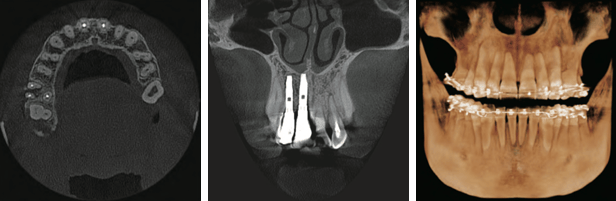

MAR(Metal Artifact Reduction) メタルアーチファクト低減機能

MAR(メタルアーチファクト低減)

RAYSCANα(3D Edge)の独自アルゴリズムを使用したCBCT再構成技術は、特別なデータ処理や作業を要することなく、アーチファクトやメタルシャドウなどの画像に影響する歪みを大きく減少させます。